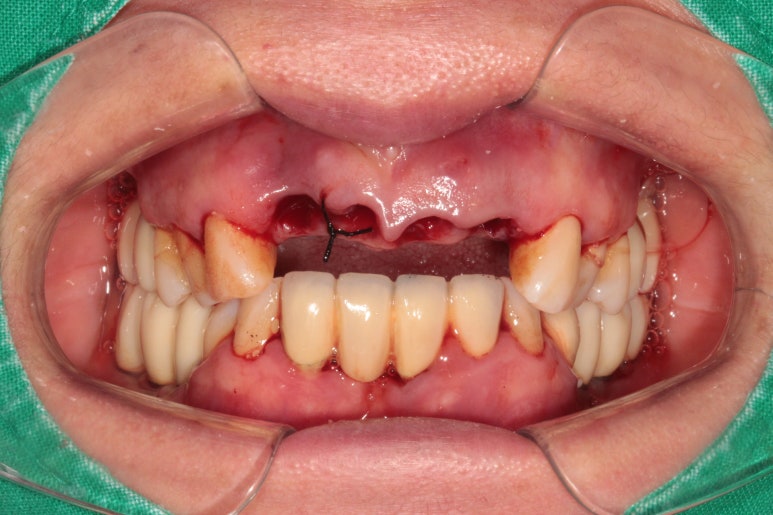

위턱 양쪽 가운데 앞니와 가쪽앞니 총 4개를 제거하기로 했습니다.

이미 내부에 고름이 너무 많이 형성되어 있었기 때문에, 네개의 앞니는 제거하기로 설명드렸습니다.

그 동안 너무 많이 고생하신 상태여서, 환자분도 흔쾌히 동의하셨습니다.

고름이 많아 염증소견이 가득했던 부위가,

치아를 제거하고 6주 정도 지나면 이렇게 말끔하게 나아있습니다.

그렇지만 내부에 잇몸뼈는 생기지 않은 상태입니다. 눈에 보이는 잇몸만 그럭저럭 나아있는 상태죠.